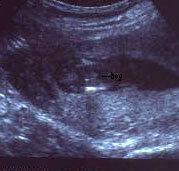

الولد

ولد في الاسبوع ال16